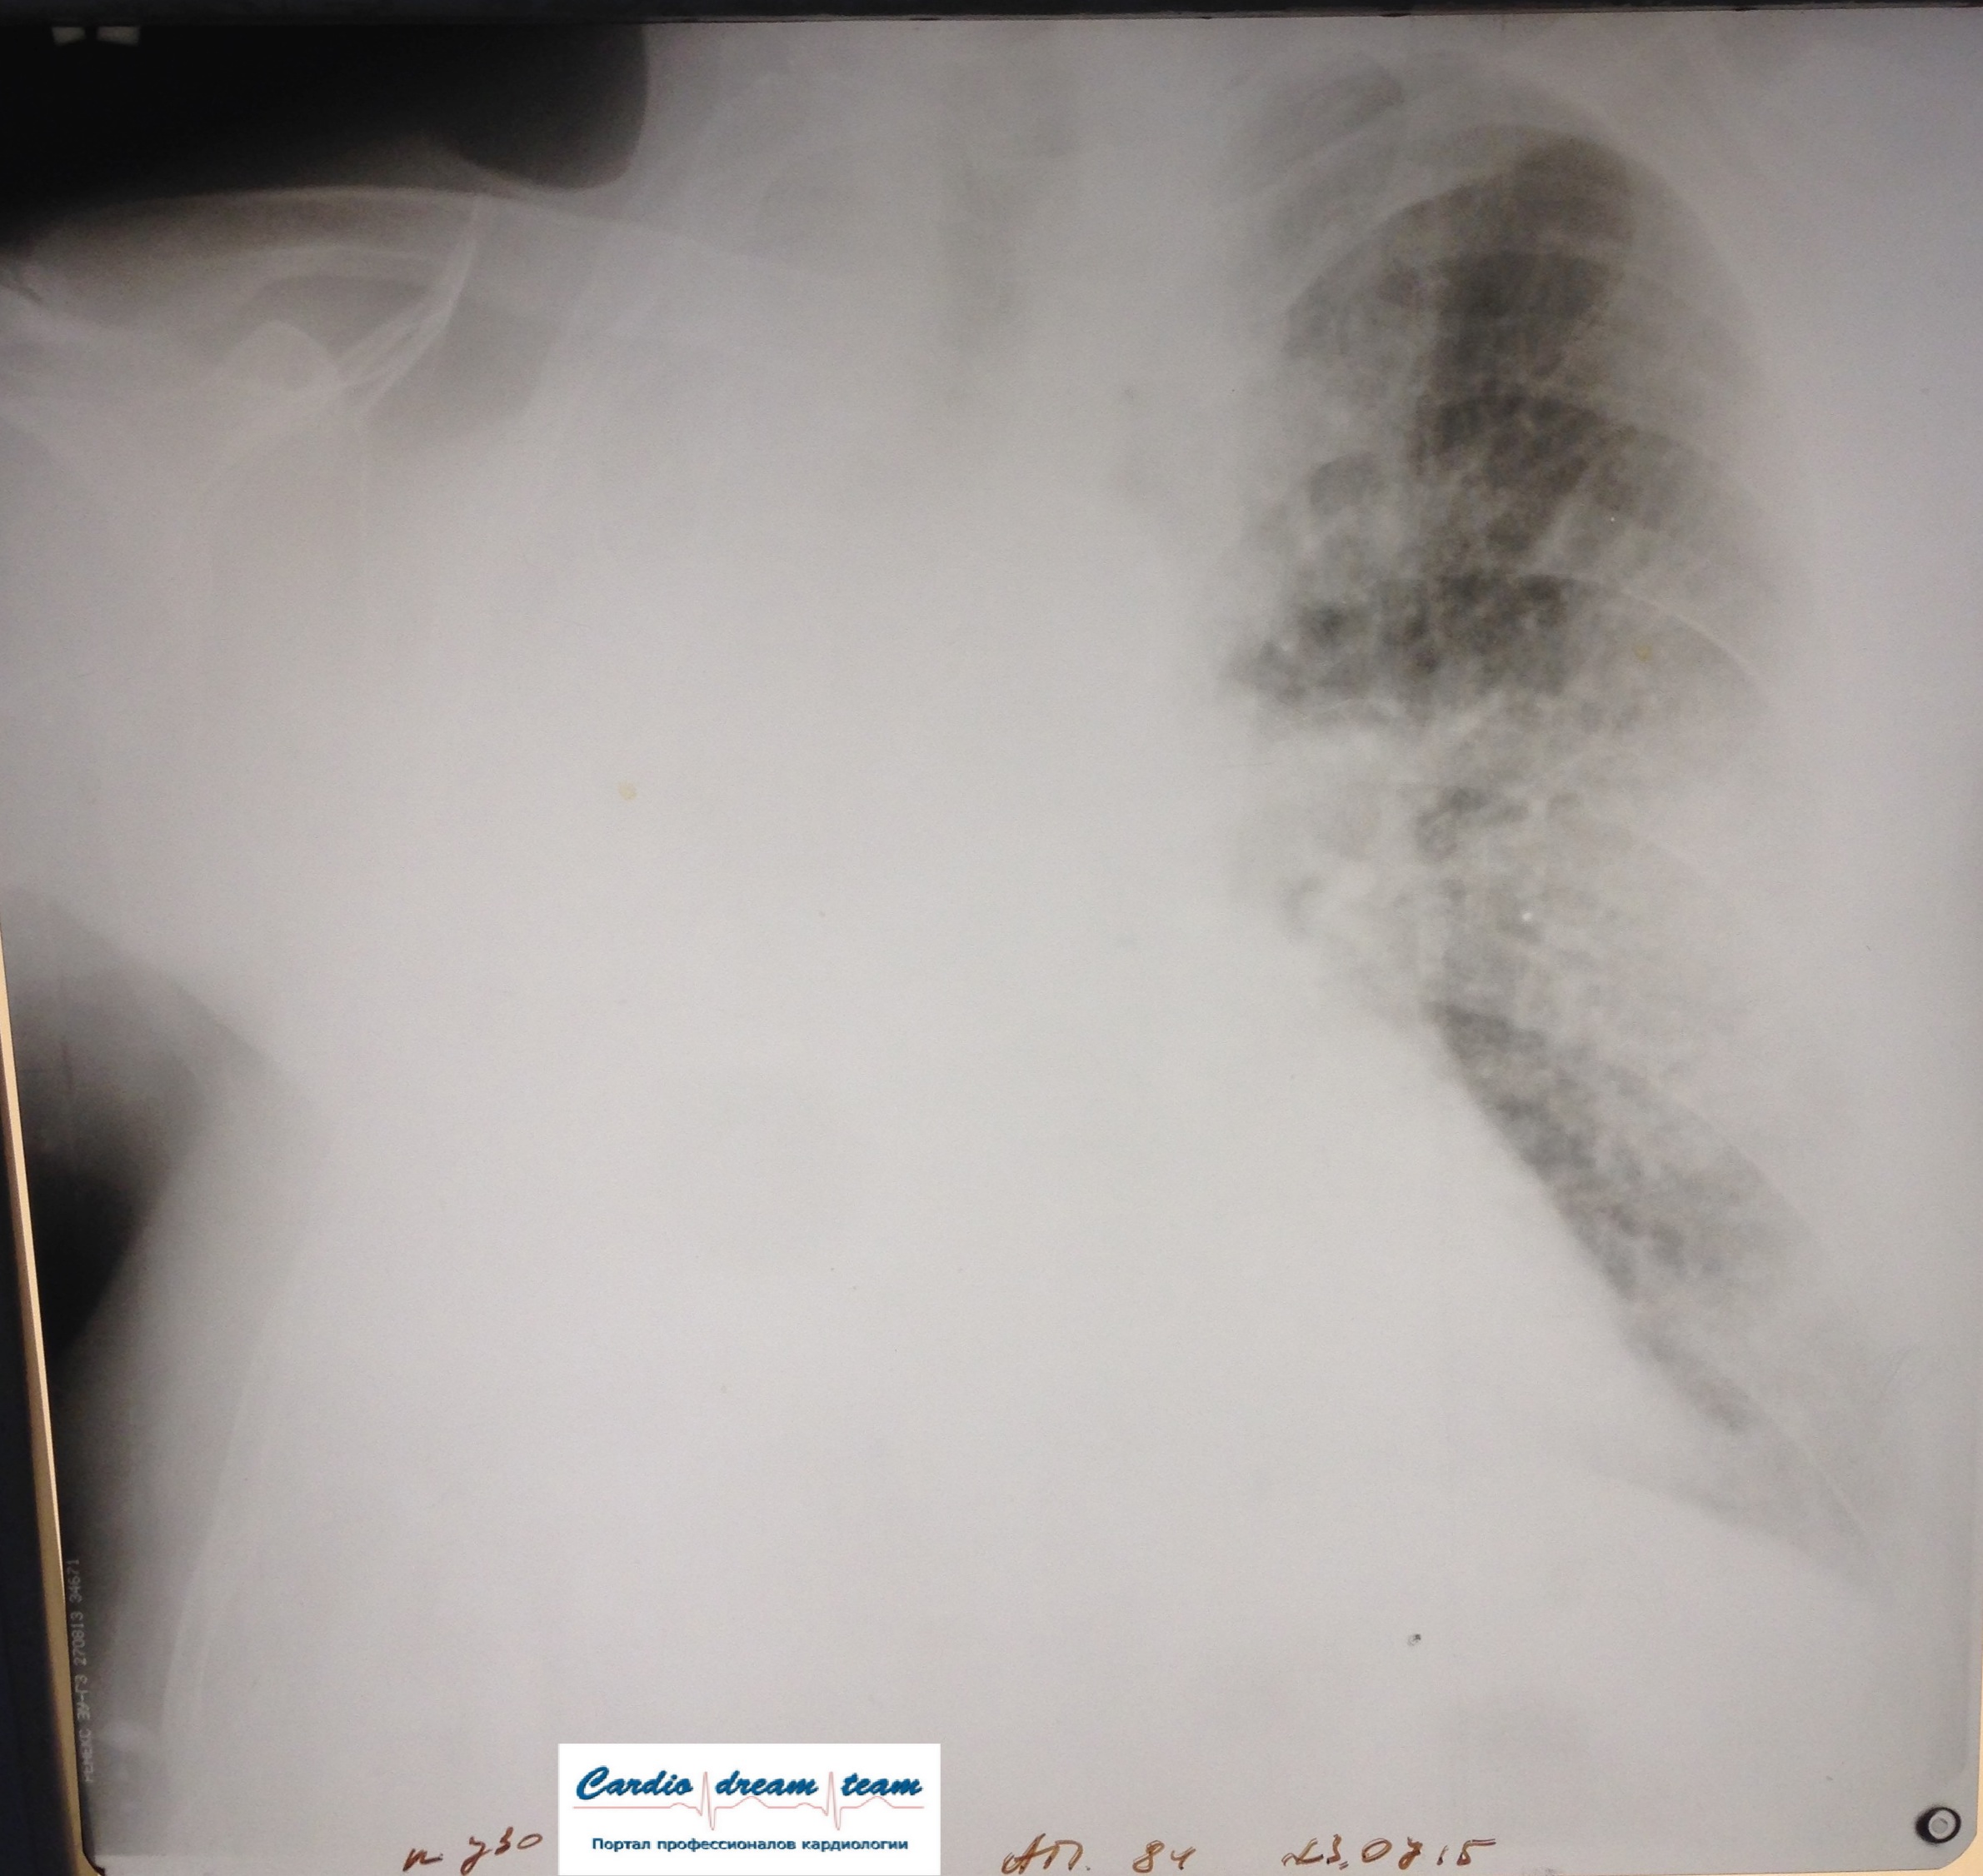

Правое легкое удалено в 1990 году. Была онкология.

Среднедолевая пневмония. Слева легкого нет.